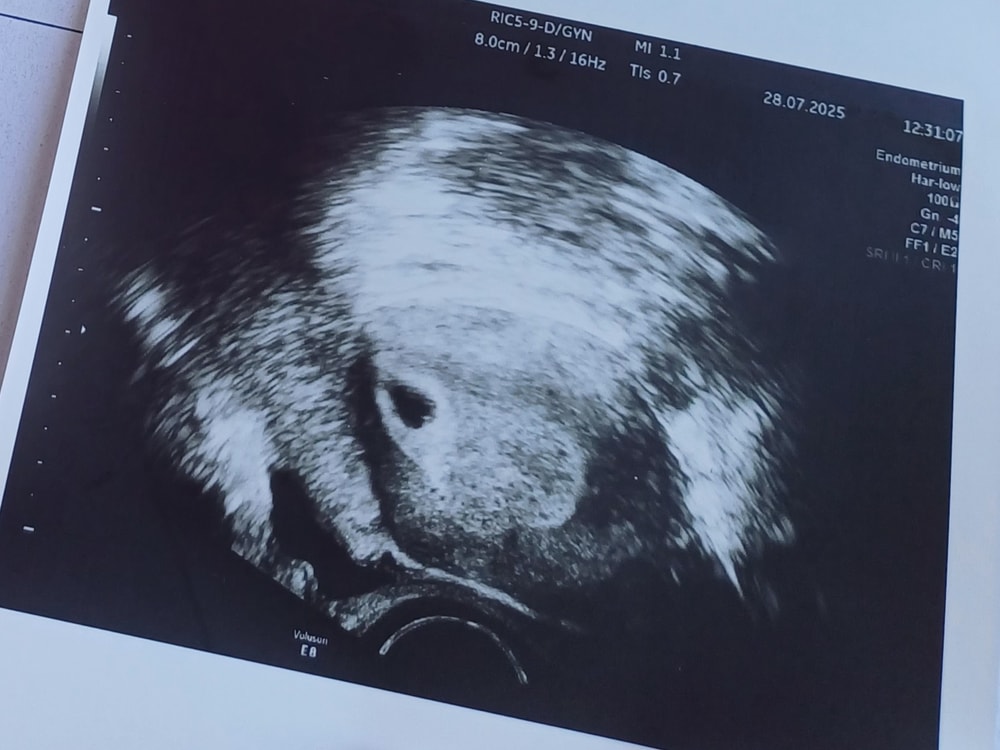

Результаты УЗИ21 дпп, мы на узи:

Маленькое счастье - 7мм ПЯ, 2,8мм ЖМ